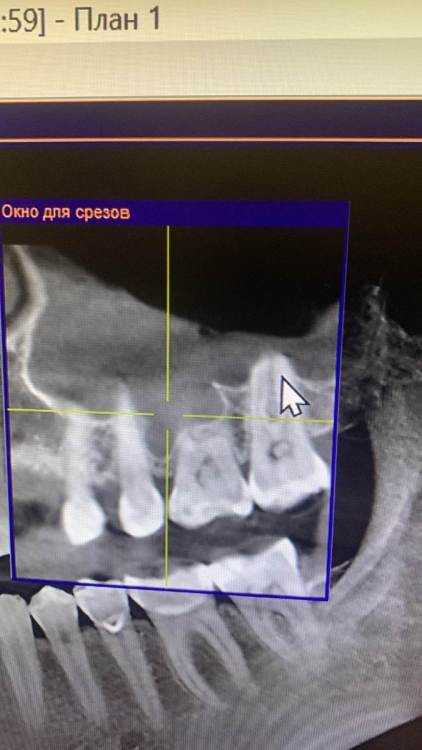

KOCTb Опубликовано 1 января, 2024 Поделиться Опубликовано 1 января, 2024 Здравствуйте коллеги. Может кто-то подскажет полезного. Пациентка. Лет 6 назад пришла с симптоматикой пульпита во втором секторе. На некоторых зубах были пломбы, без криминала. Зубы были проверены на витальность. Все живые. Пальпаторно передняя стенка ВП давала лёгкую чувствительность. Сделали КТ. Апикальных изменений не выявлено, а в пазухе слева признаки гайморита. Заполнена была бальше чем наполовину. Отправил к ЛОРу. Пролечили. Анатомическое строение не очень понравилось. С тех пор каждую зиму у неё обострение ВЧ синусита слева. Иногда даже два раза бывает. Каждый раз ЛОР в направляет к стоматологу и говорит, что гайморит одонтогенгый. Врачи рентгенологи в описании иногда там находят одонтогенгую кисту… Года два назад пациентка сходила поменяла все пломбы, на всякий пожарный. Со слов зубы все были витальные при лечении. Ну и собсвенно опять ВЧ синусит. Смущает анатомическое строение между 25 и 26 зубом. Не может ли там через периодонтальную щель «сифонить» ? Говорит между зубами иногда какой-то дополнительный дискомфорт есть. Ссылка на комментарий

KOCTb Опубликовано 15 января, 2024 Автор Поделиться Опубликовано 15 января, 2024 19 часов назад, Astronaft сказал: Здравствуйте. 6 лет назад: подробнее про симптомы пульпита? как полечили гайморит и чего добились? Анатомия действительно интересная. Интуитивно, или естественная впадина которая способствует застою либо проблемы в соустье вызывают застой и кислотный секрет лизирует самое слабое место. Опять же интуитивно, пациентке приказать зубы не трогать, не ходить выискивать проблемы. Очень подробно расспросить анамнез, в том числе что помогает, что запускает синусит. Если соустье открыто то я бы рекомендовал регулярно промывать физраствором с ЭДТА и выждать. Здравствуйте. Ну как обычно пульпитная симптоматика при ВЧ синусите. Разлитые периодические боли в верхнем секторе, с непонятной локализацией. Пальпаторно передняя стенка ВЧ пазухи давала болезненность. От 25 до 27 зуба. На КТ зубов затенение в ВЧ пазухе. Отправил тогда к ЛОРу. Подробности лечения у ЛОР врача тогда не знаю. Синуситы в холодное время года. Соустье пародонтальным зондом не выявлено. Носо-ротовая проба также отрицательная. Но тут и понятно если и есть ход, то крайне мизерный. Там слизистой завалено всё. Ссылка на комментарий